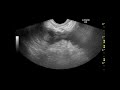

Увеличение гемоглобина может быть связано с определенными видами рака, такими как опухоль почек (рак почки), опухоль печени (гепатома) или определенные виды лейкемии. В этих случаях, повышенное количество эритроцитов может приводить к увеличению уровня гемоглобина.